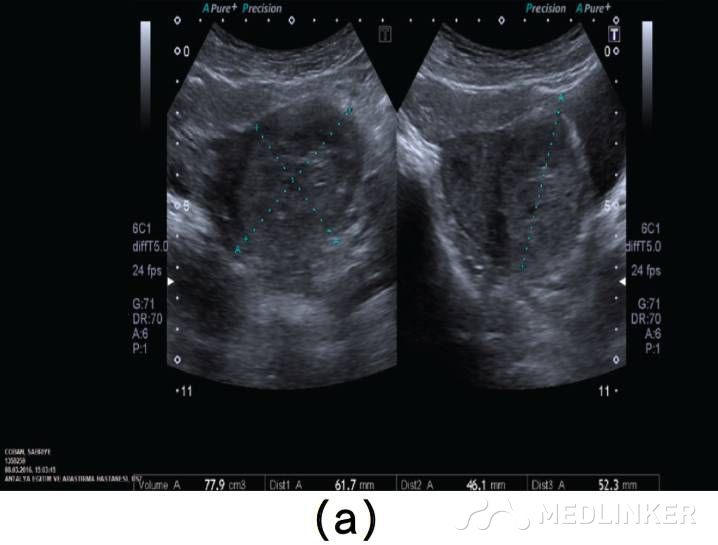

患者35岁,G2P1A1,2周前因稽留流产(9周),于外院行刮宫术(图1a)。该患在首次刮宫术后因怀疑宫腔内血肿,在术后观察的一周内反复性刮宫。最终因为患者阴道流血及转入我院后,终止刮宫。入院后查:Hb:11.2g/dL,Htc:35.1%,hCG:3518mIU/mL。阴式超声示子宫前壁可见60×60×56mm(103cm3)大小杂乱回声区(图1b)

图1 (a)刮宫术前彩超示: 宫内死胎, 妊娠9周, 未见子宫动静脉瘘;(b)子宫前壁可见大小60×60×56mm(103cm3)杂乱回声区, 并延伸至子 宫左侧 ;(c)彩色多普勒超声检查示极丰富“五彩镶嵌”彩色血流